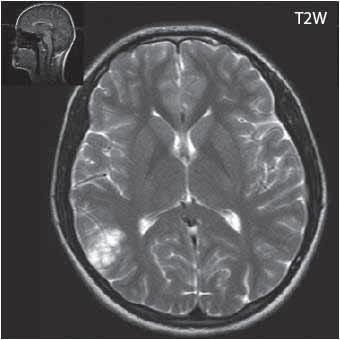

I 2 1 Difuzní astroc ytom low grade

I 2 2

I 2 3

I 2 4

astrocytom